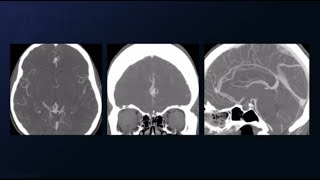

Brain Aneurysms | Updates on Unruptured Intracranial Aneurysms

In this video Omar Chouddhri, MD, Co-Director of Cerebrovascular & Endovascular Neurosurgery at Penn Medicine, offers an ...

Clipping of a Ruptured Multilobulated Middle Cerebral Artery Aneurysm

This installment of Seven Series shows the clipping of a ruptured, multilobulated middle cerebral artery (MCA) aneurysm.